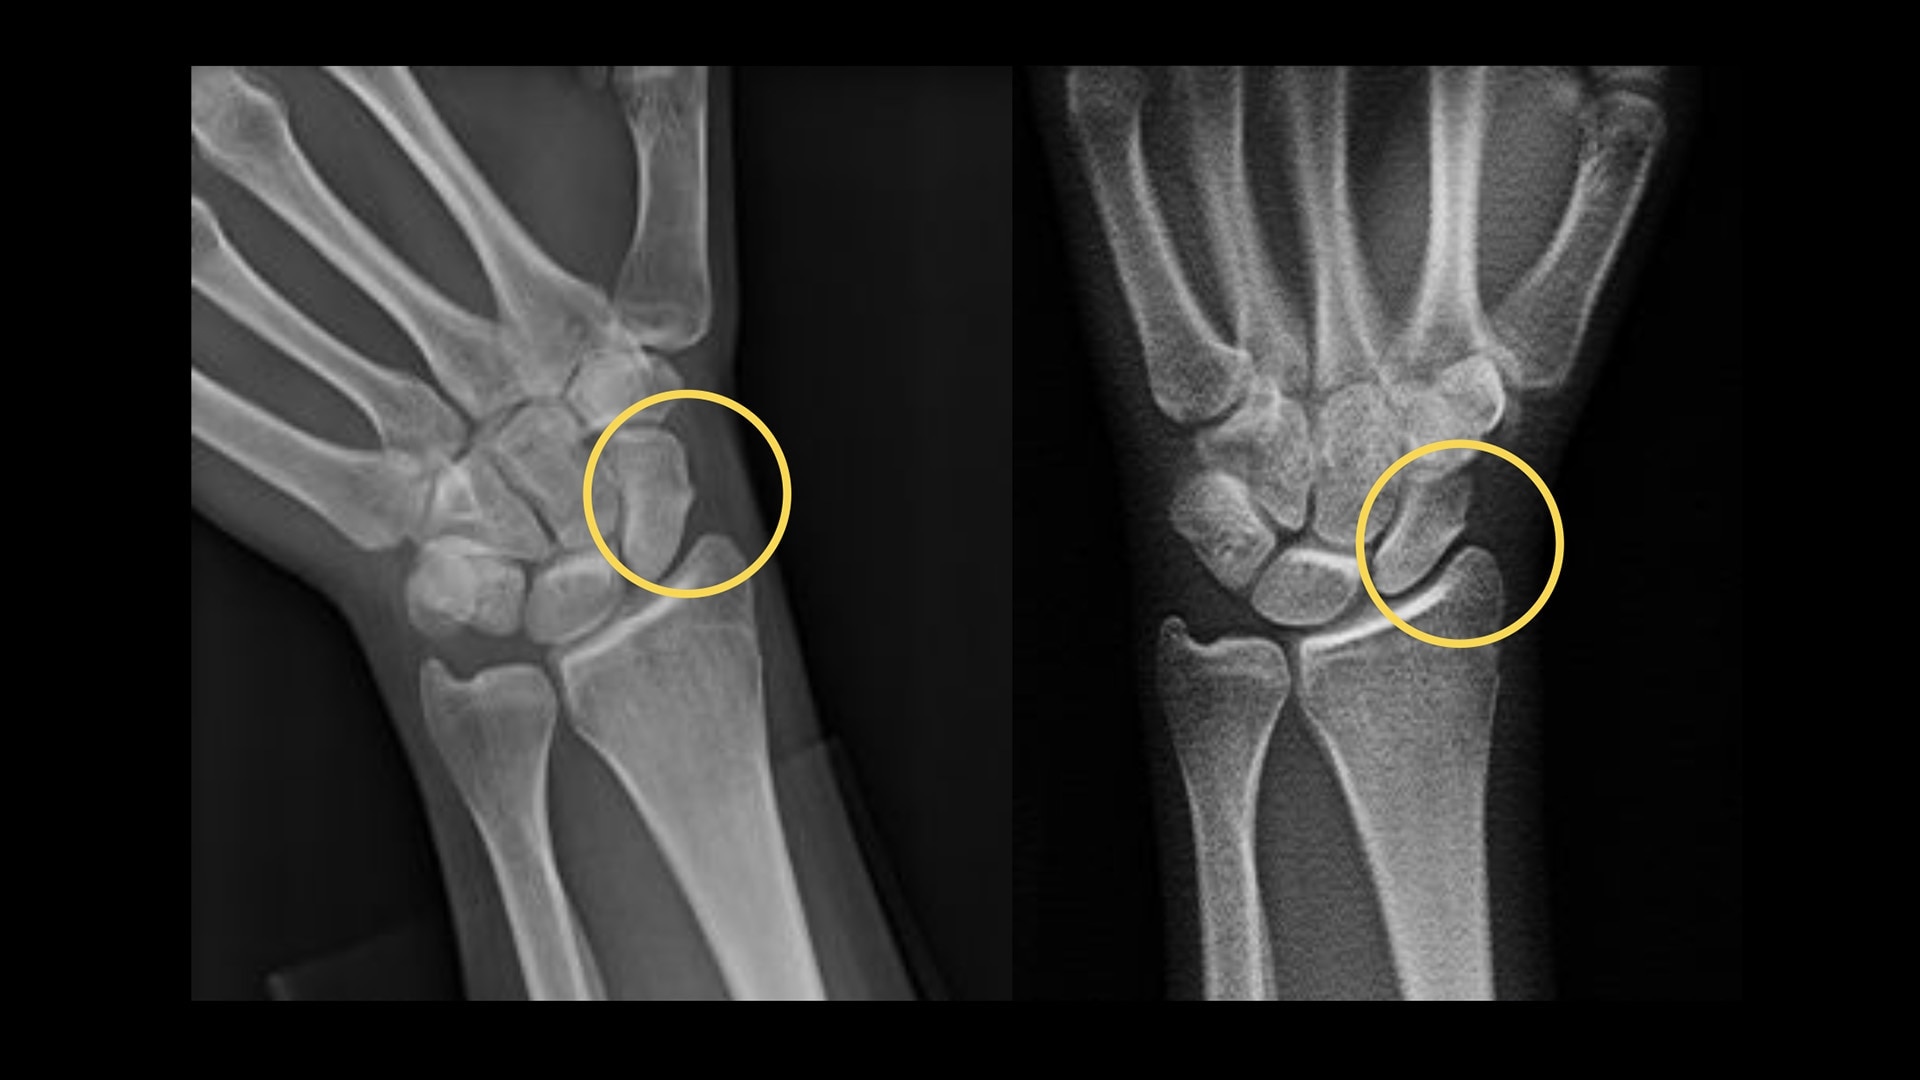

Metal artifact reduction

VolumeRAD Metal Artifact Reduction (MAR) provides quality multi-level image slices even with metal implants

Metallic implants often cause difficulty in digital tomographic imaging. Often black lines appear in the X-ray (an undershoot) or a white ring appears around the metal or there is streaking throughout the image. VolumeRAD Metal Artifact Reduction removes these effects, improving visibility, enabling analysis of implant placements and increasing clinical confidence.

Image caption: Wrist fracture with metal implant | Conventional (left) vs. VolumeRAD with Metal Artifact Reduction (right)